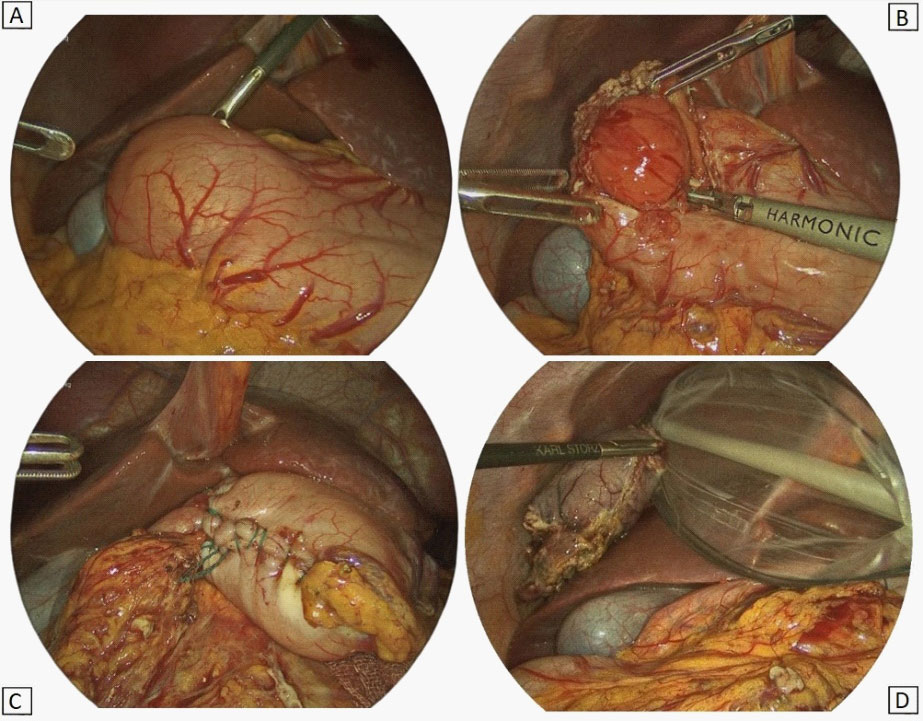

MRI scans of the abdomen confirmed a solid oval mass of 4 X 2,5 cm, with regular profiles (Figure 2). The mass arose from the pyloric antrum with upstream stomach dilated by fluid. It showed an hyperintense signal in T2-weighted sequences with no diffusion restriction to the ADC map and homogenous post-contrast enhancement. Imaging was suggestive of mesenchymal tumour.

Figure 2:Magnetic resonance imaging findings of the abdomen – MRI showing a mass developing inside the wall of the antrum with well-defined profiles. The lumen of the stomach is partially obliterated by the lesion. (A): Axial scan; (B): Sagittal scan; (C): Coronal scan.